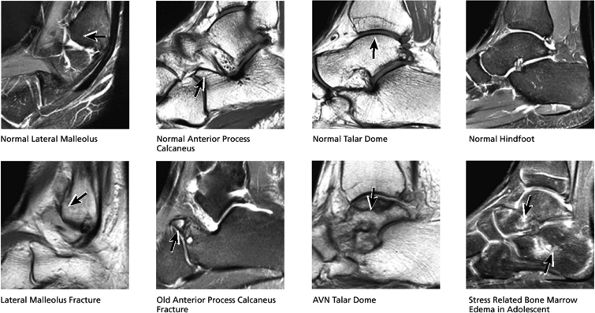

-

Osteochondral lesion of the talus (OLT) is the accepted terminology and should be used in place of transchondral fracture, osteochondral fracture, or osteochondritis dissecans.

Osteochondral lesions may involve the posteromedial or anterolateral talus.

It is important not to overestimate the size of the lesion by including adjacent marrow edema in the dimensions of the lesion proper.

Stage I: Subchondral trabecular compression. Radiograph results are negative, bone scans are posi-tive, and marrow edema is seen on MR imaging (Fig. 5.95).

Stage IIA: A subchondral cyst (Fig. 5.96)

Stage IIB: Incomplete separation of the fragment (Fig. 5.97)

Stage III: Fluid around a nondetached, nondisplaced fragment (Figs. 5.98 and 5.99)

Stage IV: A displaced fragment (Fig. 5.100)